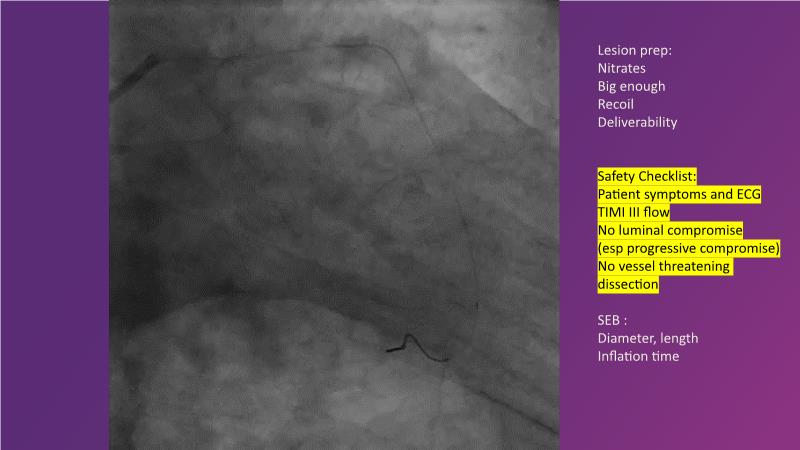

Explore the latest trends in percutaneous coronary intervention (PCI) in this session, focusing on stentless PCI and the role of sustained limus release technology. Join the discussion on how sustained limus release can expand the indications for drug-eluting balloons (DEB) and minimize the use of metal stents, gain insights into the importance of vessel preparation and learn which tools to utilize in specific scenarios.

- To discuss how sustained limus release technology can broaden DEB indications and reduce metal

- To learn about the importance of vessel preparation and which tool to use when

- To review clinical scenarios when a stent is not required